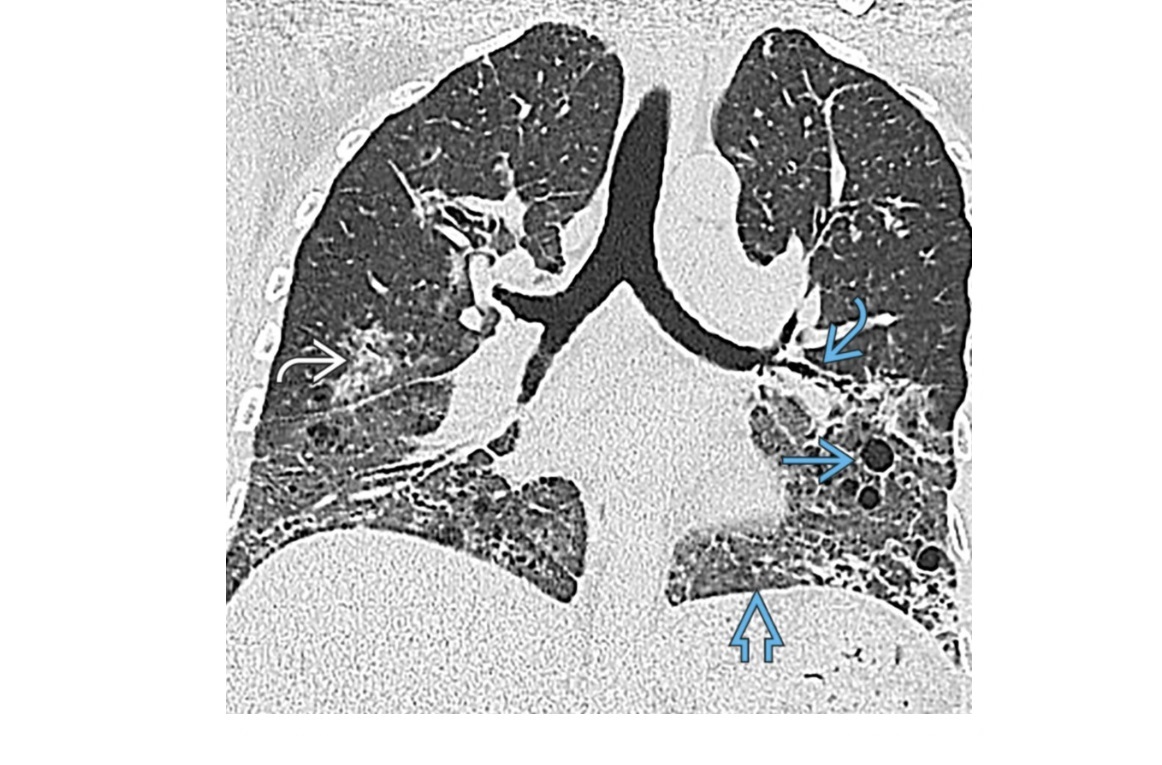

DIP

Bilateral, lower zone predominant ground-glass opacities

± subpleural **intralobular lines/retiuclations **

Small, round,** thin-walled** (2-4 mm in diameter)

Spectrum/similar HRCT to RB-ILD